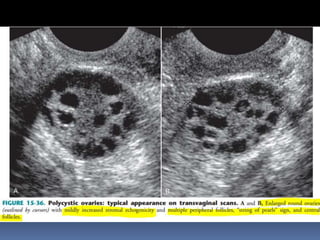

This document contains an image gallery from Dr. Mohit Goel showing various uterine anomalies and ovarian cysts. It includes images of an arcuate and unicornuate uterus, endometritis, a twisted ovarian pedicle, dermoid cysts of varying sizes and echogenicity containing hair, fat, and calcifications, and a combination dermoid cyst showing both mesh and plug structures. The gallery provides ultrasound images of different gynecological conditions for medical education and reference.